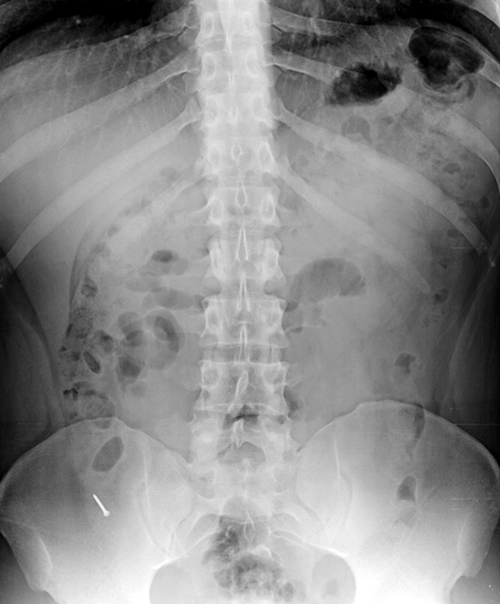

Zur Routineuntersuchung des bis dahin gesunden Patienten gehörte auch eine Röntgenaufnahme des Abdomens. Diese zeigte einen 3 cm langen, metallischen Fremdkörper im rechten unteren Quadranten. Zur weiteren Abklärung wurde der junge Mann stationär aufgenommen, schreibt das Team um Jaime M. Cevallos vom Hospital San Francisco in Quito.

Bei einer Röntgenuntersuchung im Rahmen einer Routinediagnostik entdeckten die Kollegen aus Ecuador einen metallischen Fremdkörper im unteren rechten Abdomen. Bei einer Röntgenuntersuchung im Rahmen einer Routinediagnostik entdeckten die Kollegen aus Ecuador einen metallischen Fremdkörper im unteren rechten Abdomen. © Cevallos JM et al. Jour Surg Case Rep 2019; rjy335